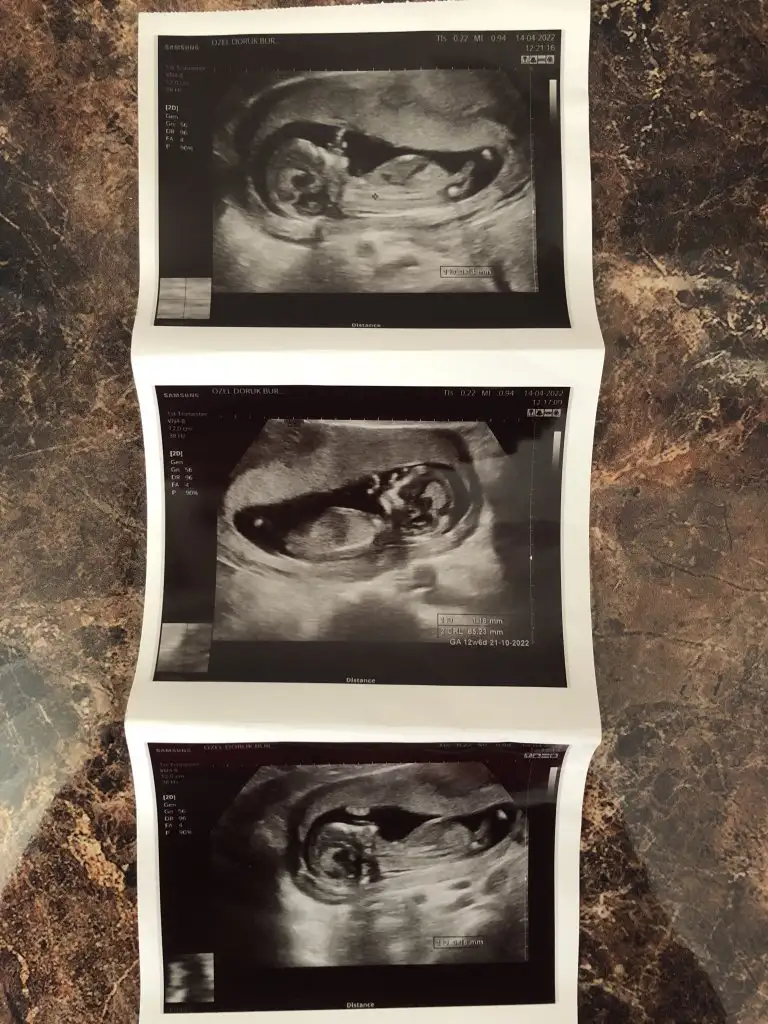

Merhaba 12+1 karından daha da büyüdüm ama öğrenmedim merakla bekliyorum :)

12 hftadan yorumlar mısınızkuzum 5-8 haftalıkları Ramzi daha büyükleri Nub teorisine göre yorumluyorum o yüzden iki teorinin birbirini tutmadığı elbetteki oluyor

ilk foto kız ikinci foto hala erkek gibi. Baksana kuzuum ilkinde bebeğin uzandığı yer paralel düz gibi , ikincisinde yukarı kayan bir şekli var. Keşke doktorlar gibi bizde hareketli anlarına baksak. Doktlar bence 13 haftalarda cinsiyet söyleyebilir ama korkuyorlarSelamlarrr yine benBu kez 11+6 usg görüntüsüyle geldim tekrar bakarsanız çok sevinirim